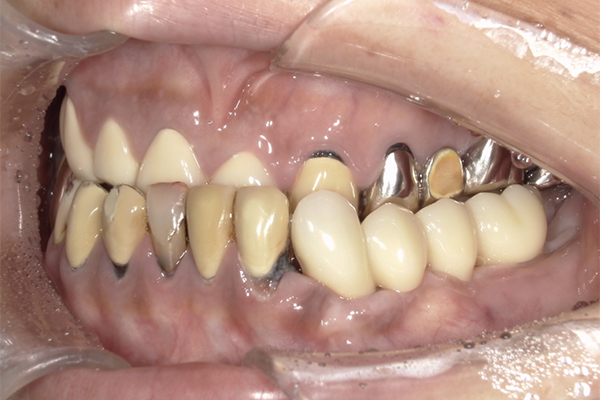

| 主訴 | 全体的にきれいにしたい |

|---|---|

| 治療内容 | 午前中に上下顎共に重度の歯周病、虫歯のため全ての歯を抜歯させていただき下顎はインプラントの土台を3本埋入し歯型を取り午後に上部構造(下顎全ての歯)を装着、上顎は一度総入れ歯を装着させていただきました。 治療が1日で完了しその日のうちに噛めるようになります。 |

| 治療期間 | 2回(1回目に資料取りをさせていただき2回目に下記の全ての治療をさせていただきました。) |

| 治療費 | 250万円 |

| 治療 リスク | 抜歯した部位などに関しては当日痛みが出ますので痛み止めなどを処方させていただきます |